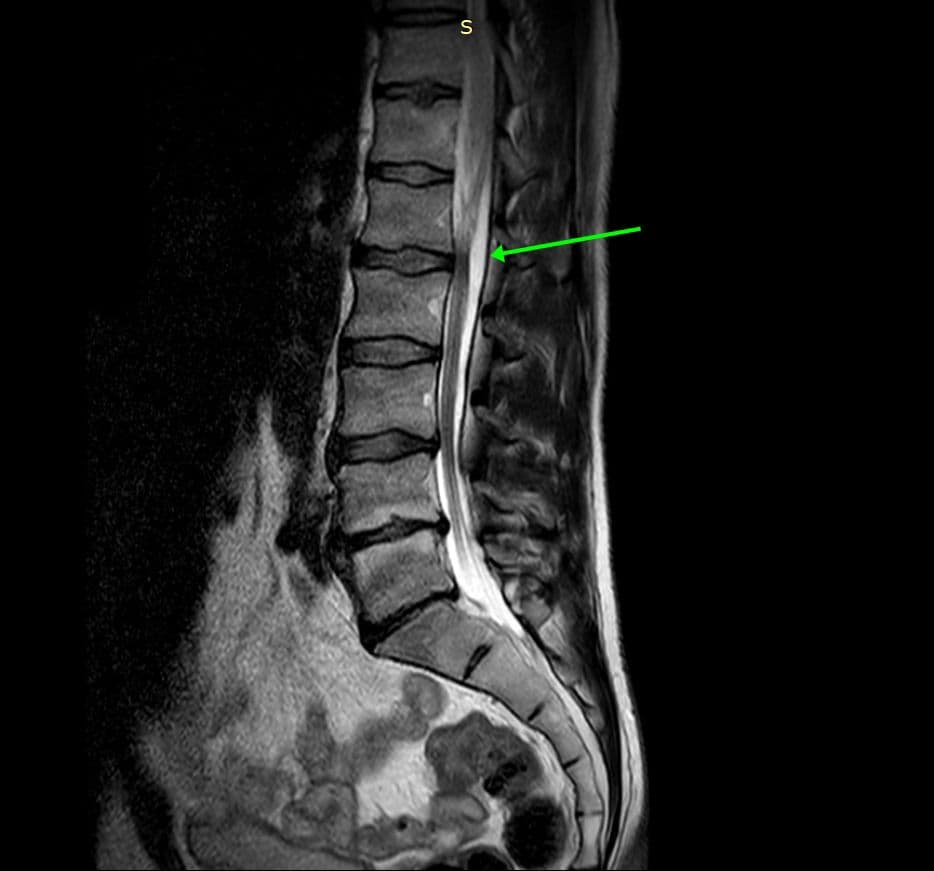

L’aspect est évocateur d’un kyste arachnoïdien épidural, rachidien, à l’origine d’un refoulement du fourreau dural.

Le contenu correspond à du liquide céphalo-rachidien. Ils se développent à partir d’une protrusion de l’arachnoïde au travers d’un defect de la dure mère, avec communication avec l’espace sous arachnoïdien spinal.